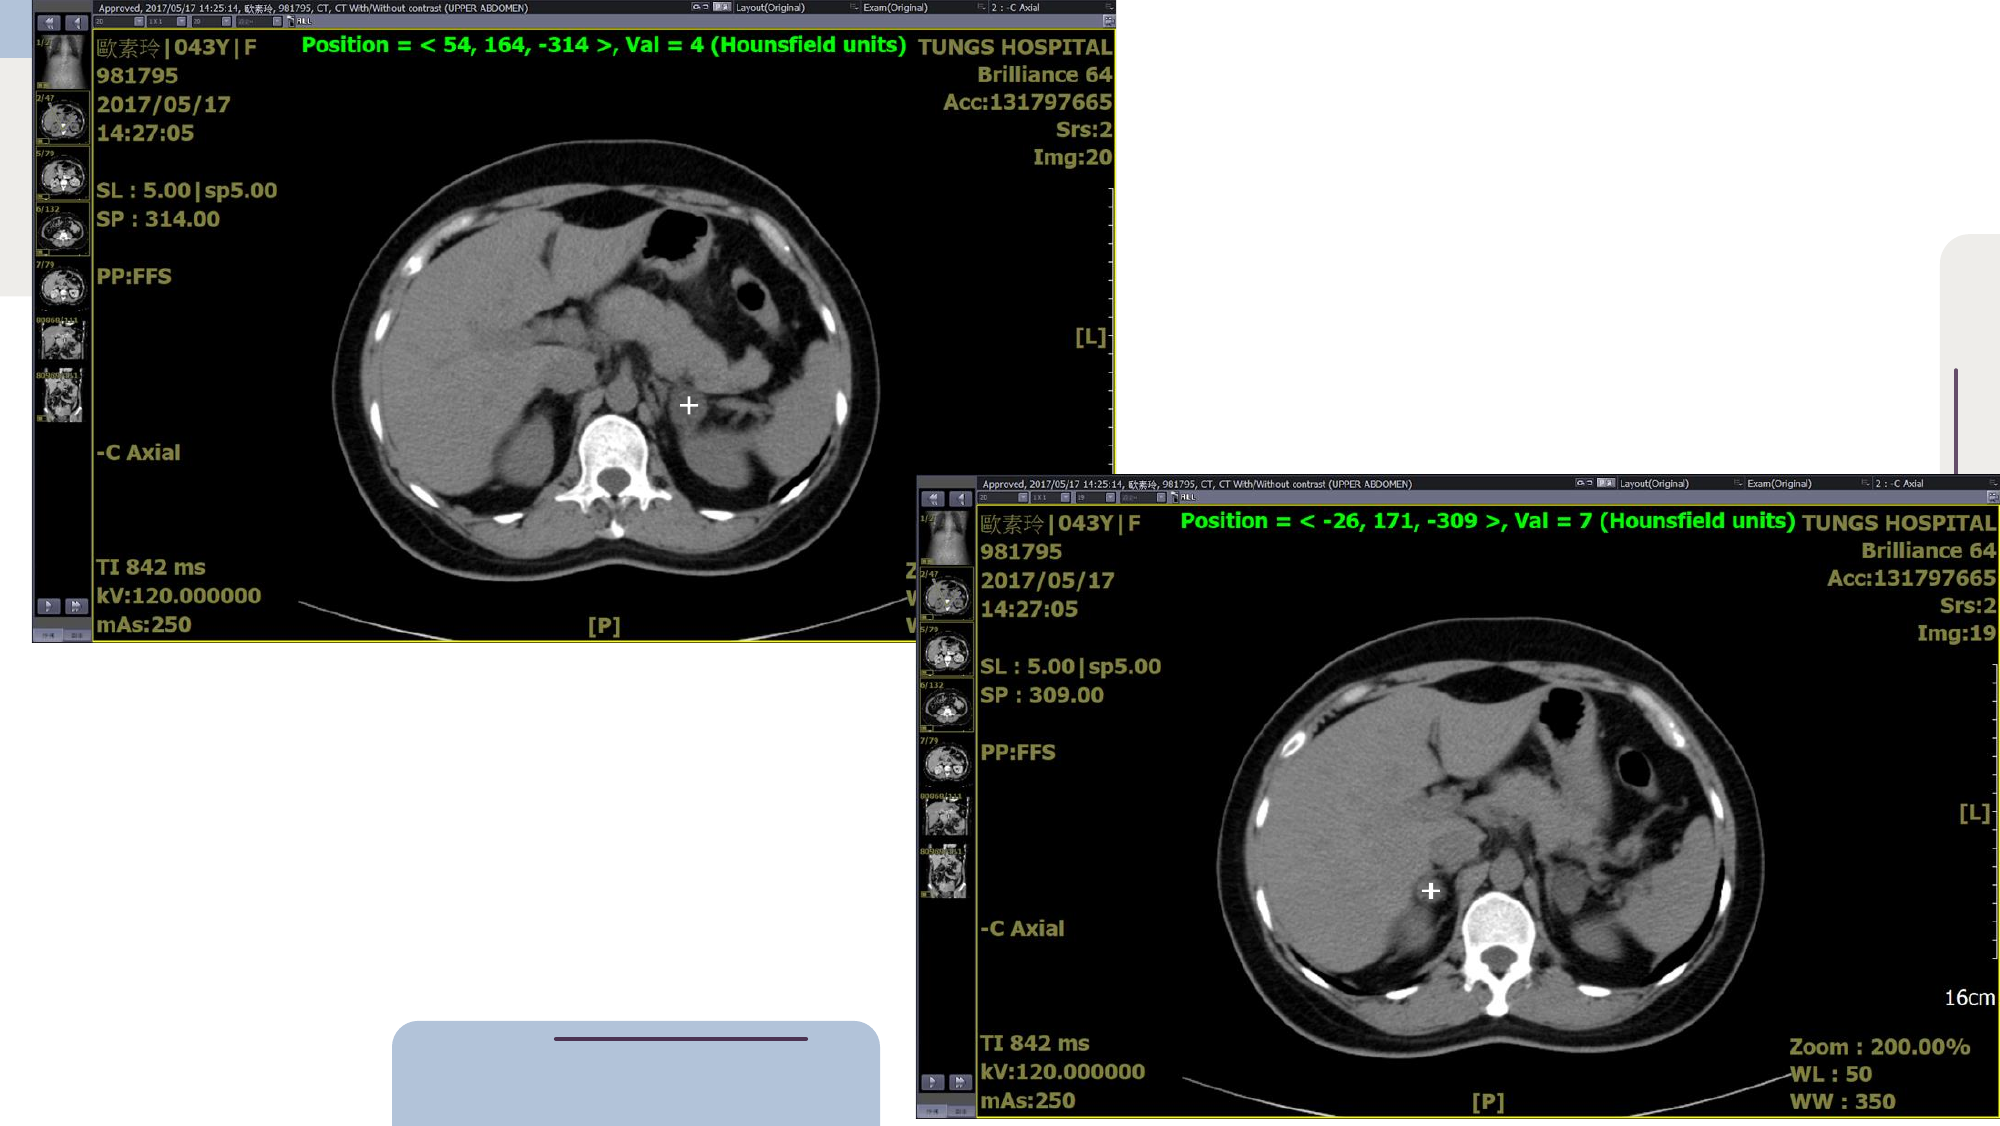

- CT HU 值 (Hounsfield Units): 透過 CT 影像判斷腫瘤密度。若 HU 值較低,傾向良性 (Benign)。

- 病人影像: 2017 年 CT 顯示左右兩側腫瘤的 HU 值均為個位數 (Low attenuation),故歸類為 Benign (良性) 腫瘤。

- Slides 延伸說明: CT 影像顯示 Right adrenal tumor 1.9 x 2.3 cm, Left 1.4 x 1.3 cm。HU < 10 通常建議無需進一步影像追蹤惡性可能,但需評估荷爾蒙。